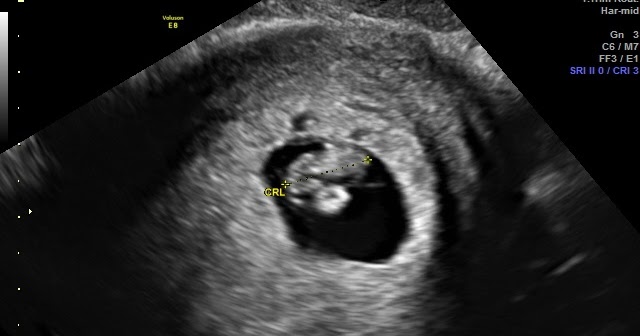

A dating scan is an ultrasound scan carried out at around 12 weeks of pregnancy, that's used to work out your due date . It's likely to be the first time you see your baby and hear their heartbeat . This scan is also used to check that your baby's development is on track and is often part of combined screening for genetic variations, such as Down's syndrome , Edwards' Syndrome and Patau's Syndrome .

It involves a blood test and measuring the fluid at the back of the baby's neck (nuchal translucency) with an ultrasound scan . This is sometimes called a nuchal translucency scan . The nuchal translucency measurement can be taken during the dating scan . If you have agreed to have screening for Down's syndrome, the dating scan and the screening will usually happen at the same time .

What else will the dating scan reveal? The scan can check that your baby's heart is beating and they are developing normally (NHS 2017a) . The dating scan isn't designed to look for subtle abnormalities, though . That will happen at your NT scan and 20-week (anomaly) scan . By 20 weeks, the sonographer will be able to see your baby in more detail because they're bigger .